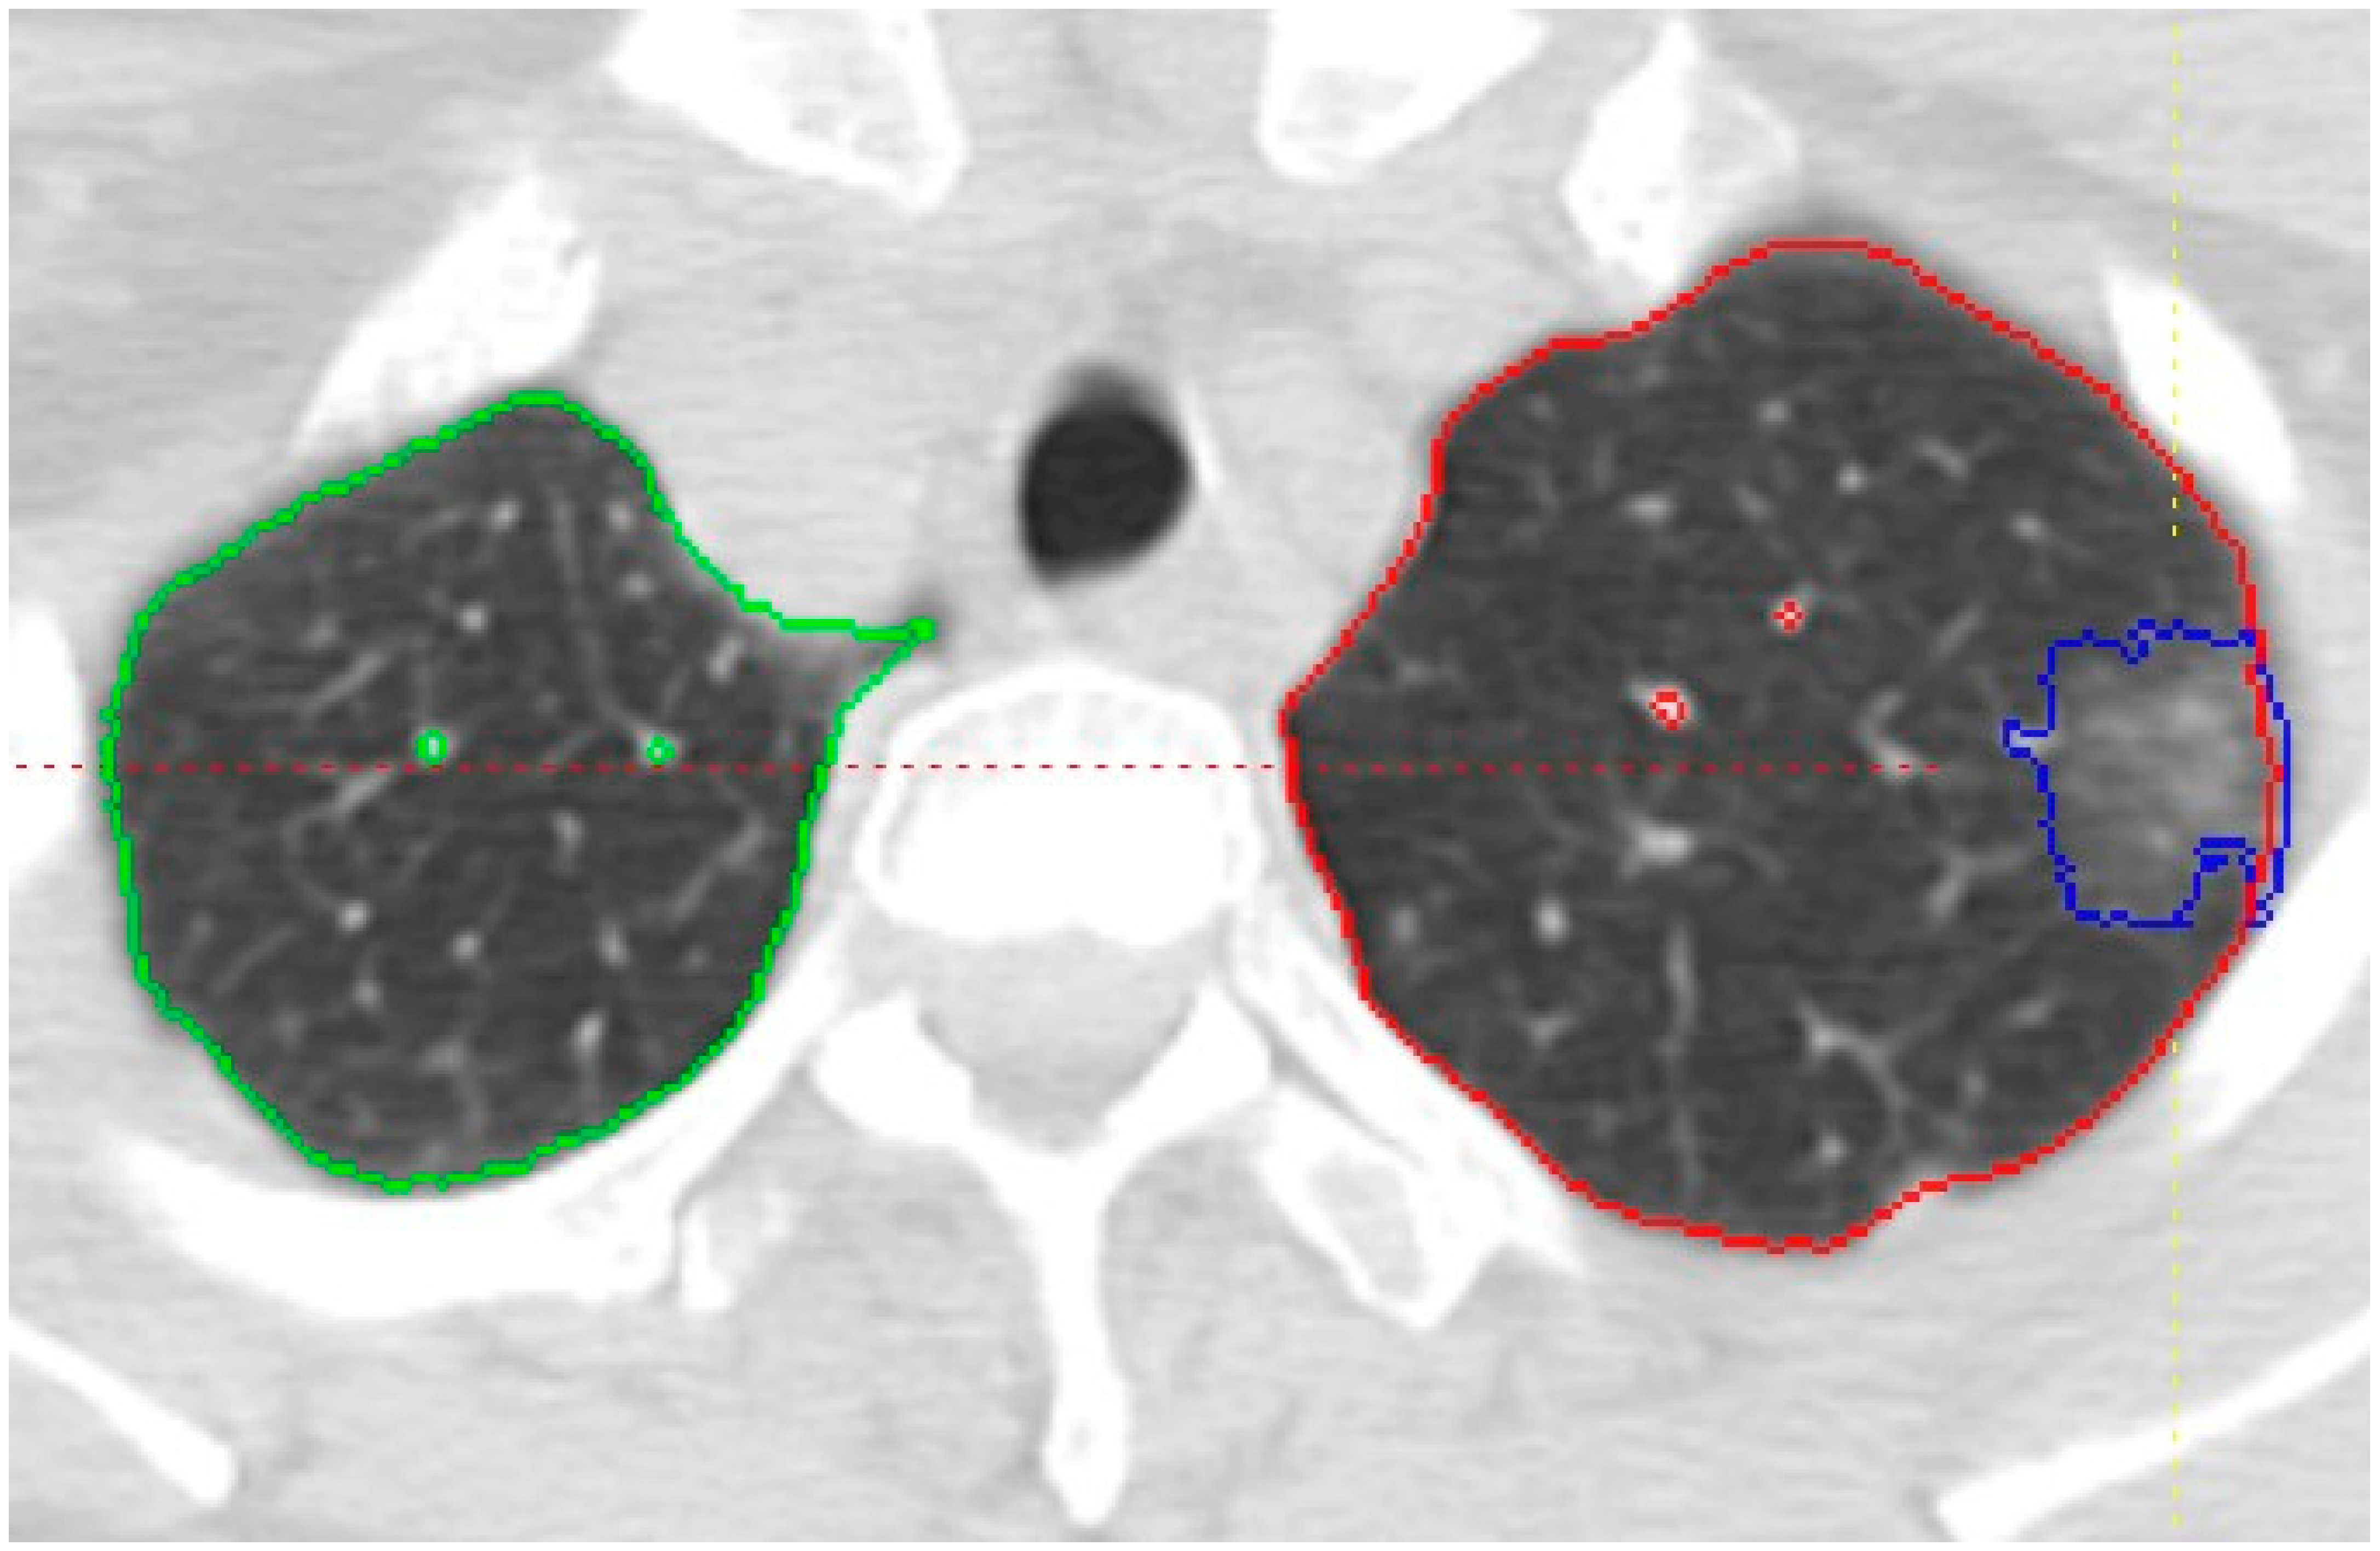

Predicting Invasiveness in Lepidic Pattern Adenocarcinoma of Lung: Analysis of Visual Semantic and Radiomic Features

3.1. Visual Read Variables

3.2. Radiomic Variables